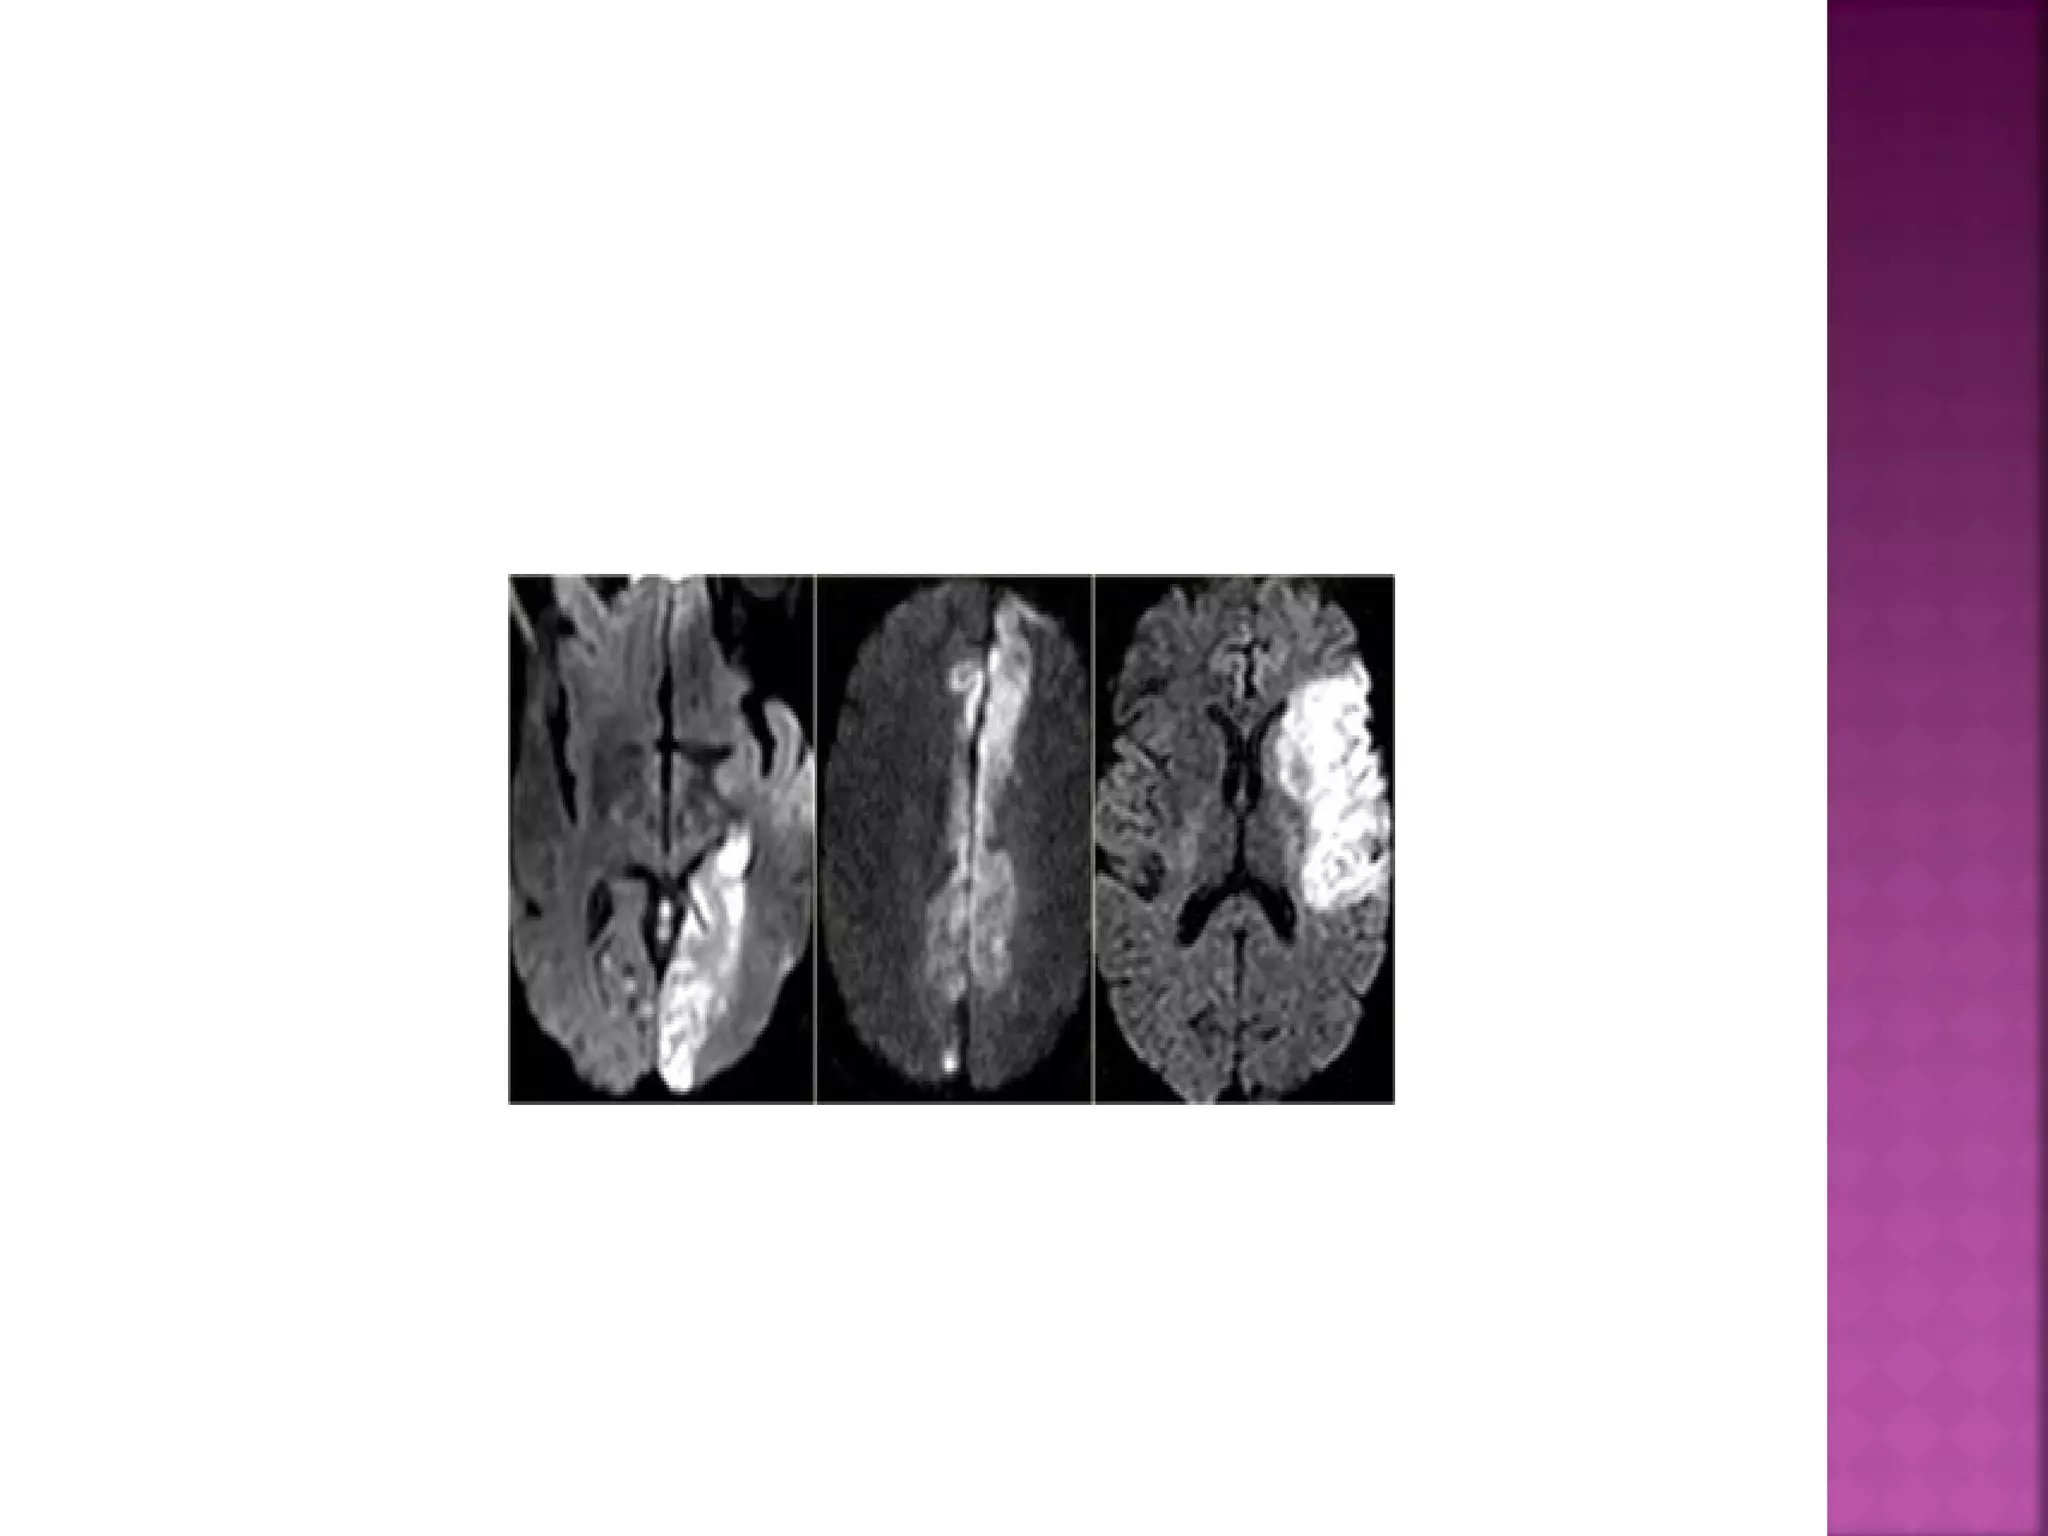

DWI is the most sensitive sequence for stroke

imaging.

DWI is sensitive to restriction of Brownian

motion of extracellular water due to

imbalance caused by cytotoxic edema.

Normally water protons have the ability to

diffuse extracellularly and loose signal.

High intensity on DWI indicates restriction of

the ability of water protons to diffuse

extracellularly.

DWI is already positive in the acute phase

and then becomes more bright with a

maximum at 7 days.

DWI in brain infarction will be positive for

approximately for 3 weeks after onset (in

spinal cord infarction DWI is only positive for

one week!).

ADC will be of low signal intensity with a

maximum at 24 hours and then will increase

in signal intensity and finally becomes bright

in the chronic stage.

 DWI is themost sensitive sequence for stroke imaging. DWI is sensitive to restriction of Brownian motion of extracellular water due to imbalance caused by cytotoxic edema. Normally water protons have the ability to diffuse extracellularly and loose signal. High intensity on DWI indicates restriction of the ability of water protons to diffuse extracellularly.

  DWI is alreadypositive in the acute phase and then becomes more bright with a maximum at 7 days. DWI in brain infarction will be positive for approximately for 3 weeks after onset (in spinal cord infarction DWI is only positive for one week!).

 ADC will beof low signal intensity with a maximum at 24 hours and then will increase in signal intensity and finally becomes bright in the chronic stage.